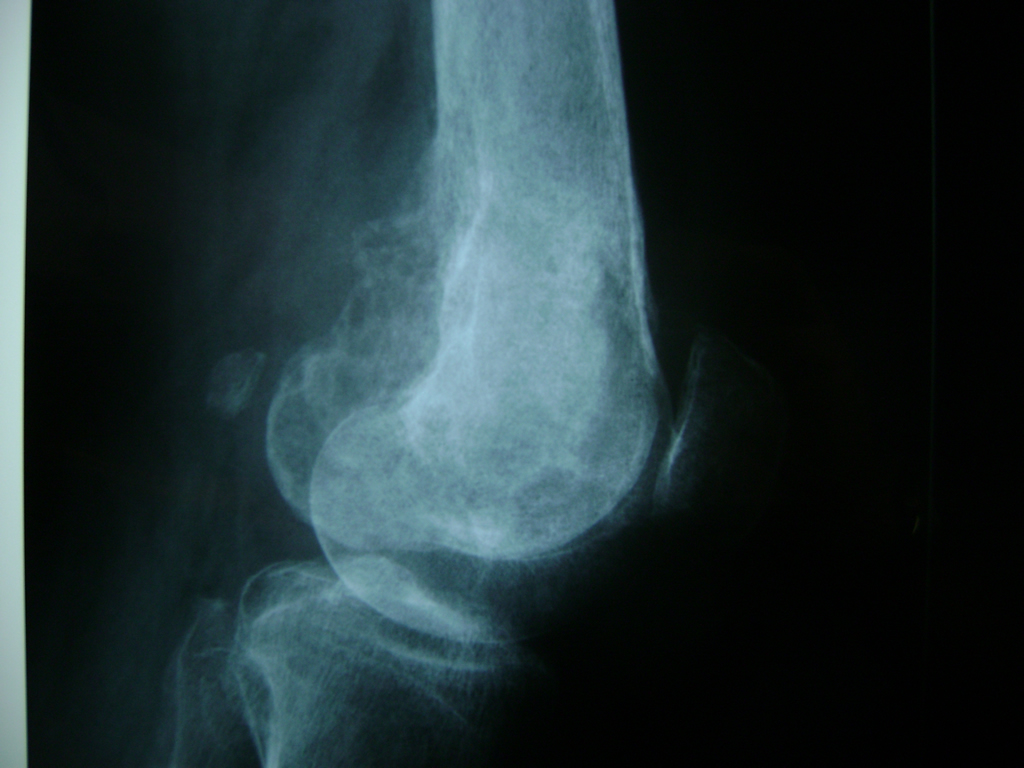

Cirugías de Húmero - Rodilla

La artroscopia de rodilla es un cirugía en el cual la estructura interna de la articulación es examinada ya sea para realizar un diagnostico o para realizar un tratamiento, este procedimiento se realiza utilizando un instrumento parecido a un pequeño tubo llamado artroscopio.